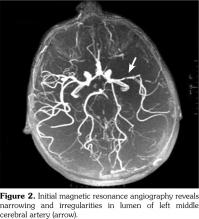

Based on these clinical findings, the patient was diagnosed as HSP, and the skin biopsy showed leukocytoclastic vasculitis with histopathologic evidence of immunoglobulin (Ig) A and M deposition based on direct immunofluorescence staining. A written informed consent was obtained from the parent of patient. The patient was being followed-up as an out-patient. On the 15th day of his follow-up, he admitted to the emergency department by sudden focal tonic- clonic convulsions and unconsciousness. He was not able to use his right hand and foot, also he could not talk. His blood pressure was 105/70 mmHg. Fundoscopic examination was unremarkable. The physical examination showed aphasia, right sided central facial paralysis, and hemiplegia on the right. Deep tendon reflexes were exaggerated and there was extensor plantar response on the right side. Cerebellar functions and sensory testing were normal. In acute laboratory evaluation, serum electrolytes and glucose levels were normal. Immediate 1.5 Tesla magnetic resonance imaging (Magnetom Avanto, Siemens Medical Solutions, Erlangen, Germany) demonstrated multiple, high signal intensity areas on T2-weighted images in both cortical and subcortical areas of the left parietal lobe (Figure 1). Magnetic resonance angiography revealed narrowing and irregularities in the lumen of left middle cerebral artery resembling vasculitis (Figure 2). Electroencephalography showed diffuse generalized delta slow waves of moderate amplitude without epileptiform discharges. Renal angiography and mesenteric vasculature were normal. The patient was diagnosed as cerebral vasculitis due to HSP. Intravenous pulse methylprednisolone (30 mg/kg/day) was given for three consecutive days; subsequently the patient received oral steroids (2 mg/kg/day) for cerebral vasculitis. Because of the unchanged clinical status of the patient, pulse cyclophosphamide therapy was begun. Patient received 500 mg/m(2)/day pulse cyclophosphamide monthly for three months. He showed clinical improvement after cyclophosphamide therapy. The follow-up magnetic resonance angiography, performed 15 days after the initial one, demonstrated substantial improvement of cerebral lesions (Figure 3). His steroid treatment was stopped by tapering within six months. He had speech therapy and also physical rehabilitation and therapy for two years. He has been followed-up without any sequel for four years.